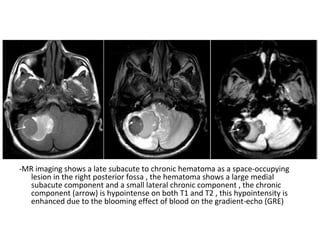

5-Mass Effect :

-Current diagnosis of CVI relies on the detection

of parenchymal edema or hemorrhage in the

presence of acute cerebral venous thrombosis

-Marked brain swelling is often seen with